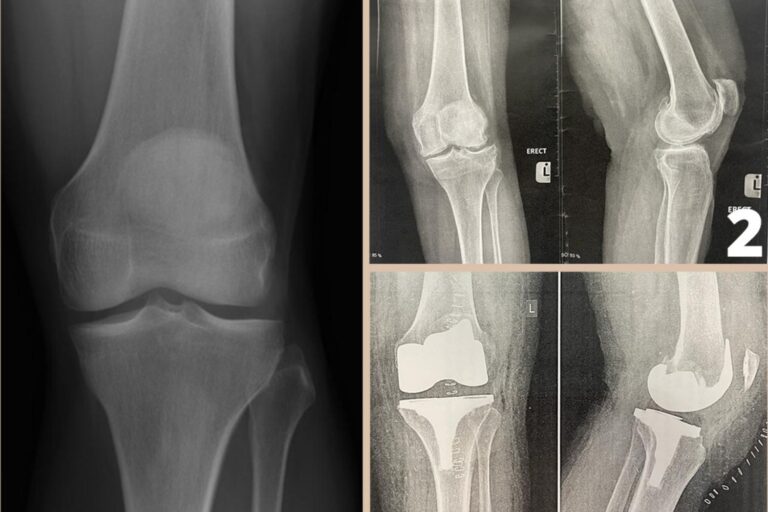

Partial vs. Total Knee Replacement Surgery Knee Replacement Surgery Hammer you will likely be well on your way to recovery 12 weeks after total knee replacement surgery. orthopedic hammers (mallets) are designed to provide controlled tap or pressure on a chisel or osteotomy bone cutting tool. during knee replacement surgery, an orthopaedic surgeon will resurface your damaged knee with artificial components, called implants. if simple treatments. Knee Replacement Surgery Hammer.

kneereplacementxray The Orthopedic & Sports Medicine Institute in Knee Replacement Surgery Hammer Knee replacement surgery is typically used as the last option in the treatment of osteoarthritis. However, you may be able to start returning. you will likely be well on your way to recovery 12 weeks after total knee replacement surgery. see what happens during knee replacement surgery in this video and learn about the surgical procedure that helps.. Knee Replacement Surgery Hammer.